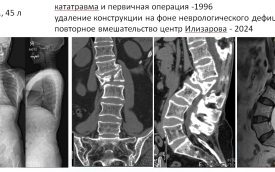

Пациентка из Республики Марий Эл получила травму позвоночника 26 лет назад. К сожалению, на родине ей не смогли оказать необходимую помощь. Лечение привело к неврологическим осложнениям, в результате которых у нее пропала чувствительность в ногах, и врачам пришлось удалить фиксирующую конструкцию для позвоночника. После этого у пациентки развилась значительная деформация позвоночника.

Когда женщина приехала в Курган, она страдала от стойкого болевого синдрома и нарастающей слабости в ногах.

Мы подобрали нужный инструмент, и каждый винт навигировали с помощью навигационной станции, что позволило удачно установить аппарат. Деформация была исправлена одномоментно, а в течение следующей недели мы продолжали восстанавливать ось позвоночника, избегая неврологических осложнений.

На втором этапе руководитель Клиники патологии позвоночника и редких заболеваний Центра Илизарова, к.м.н. Алексей Евсюков, успешно завершил операцию, установив раздвижной имплантат и зафиксировав позвоночник погружной конструкцией.